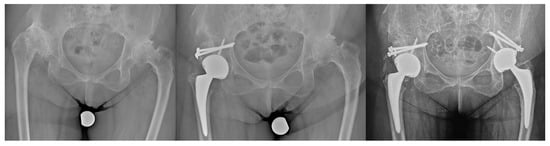

2.2. Radiological Assessment

3.2. Radiographic Results